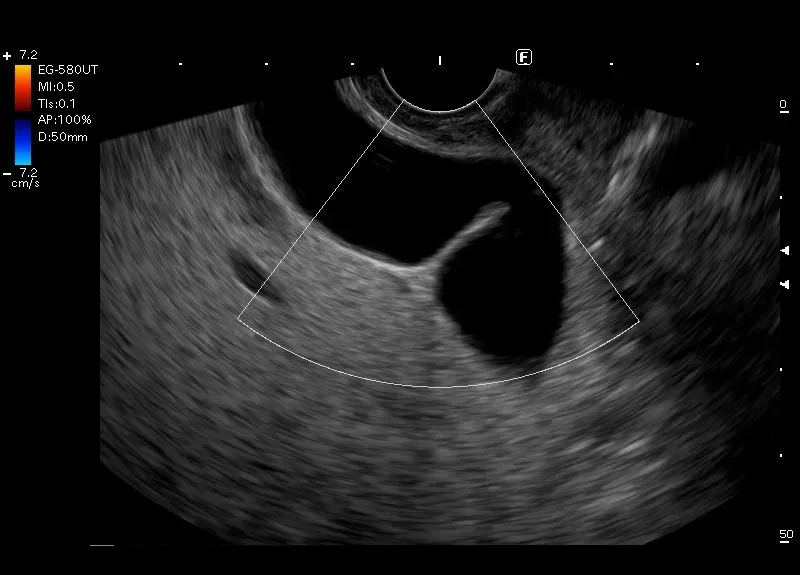

Odmiana anatomiczna p

ęcherzyka żółciowego - p

ęcherzyk żółciowy zgięty w okolicy

dna